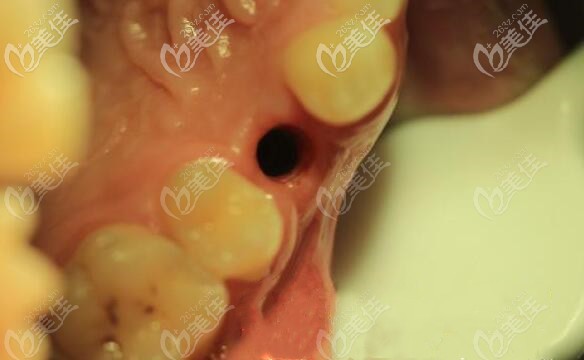

手術(shù)時(shí)間也就把半個(gè)小時(shí)就完成了,當(dāng)天為顧客戴臨時(shí)冠,